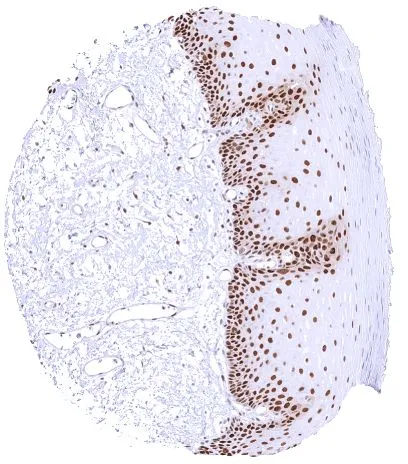

GTX644715 IHC-P Image

IHC-P analysis of human adenocarcinoma of the uterine cervix tissue using GTX644715 PCNA antibody [HMV4714] HistoMAX™.